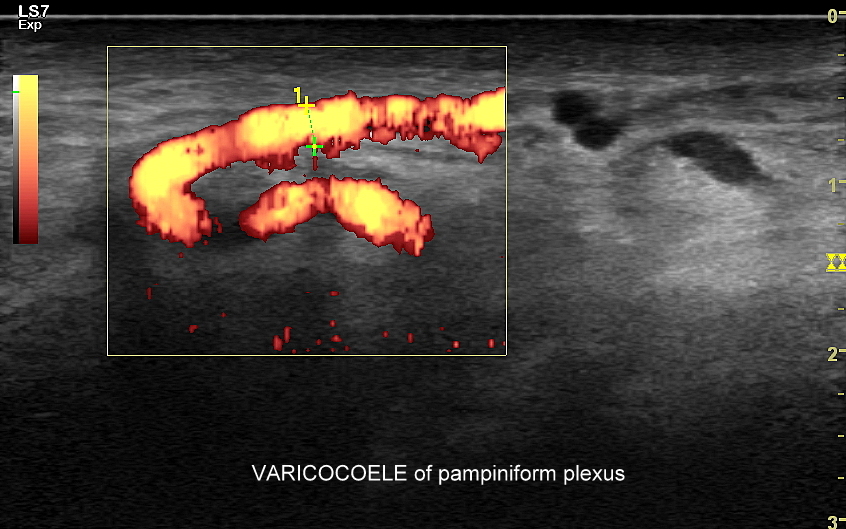

Najczęstsze choroby w obrębie moszny obejmują żylaki powrózka nasiennego, zapalenia jąder i najądrzy, wodniaki jądra, skręty szypuły jądra bądź przydatków jądra, torbiele najądrzy, nowotwory i raki jąder. Niezależnie od powyższego u chłopców spotyka się wnętrostwo, czyli niepełne zstąpienie jądra do moszny, które to może pozostać w jamie brzusznej lub pachwinie, a także ektopię jąder, czyli ich zabłąkane położenie (np. w okolicy krocza).

USG moszny i kanału pachwinowego jest podstawową metodą obrazowania jąder, najądrzy, powrózka nasiennego, w tym nasieniowodu oraz towarzyszących im naczyń żylnych i tętniczych. Badanie USG przeprowadzić należy w przypadku wystąpienia bólu i obrzęku jąder, pojawienia się macalnego guzka w obrębie moszny, podejrzenia skrętu lub zapalenia jądra, żylaków powrózka nasiennego, w ramach oceny dojrzewania płciowego chłopców. Kanał pachwinowy bada się także w sytuacji podejrzenia wnętrostwa, przepukliny pachwinowej, w celu oceny węzłów chłonnych, a także nasieniowodu w diagnostyce niepłodności męskiej.

Mosznę bada się aparatem USG wyposażonym w dedykowaną sondę o wysokiej rozdzielczości przeznaczoną do oceny jąder i drobnych struktur moszny, koniecznie z zastosowaniem trybów dopplerowskich, takich jak Doppler kodowany kolorem, Doppler spektralny i obrazowanie mikrounaczynienia. Dopełnieniem badania USG jąder jest użycie w stosownych przypadkach trybu elastografii oraz trybu USG z kontrastem (CEUS). Lekarzem, który pierwszy we Wrocławiu i na Dolnym Śląsku przeprowadził badanie CEUS jąder jest dr Tomasz Szczepański.

W celu przygotowania się do planowego badania USG moszny i pachwin u osób dorosłych i nastoletnich prosimy o ogolenie badanej okolicy. Ze względu na przeprowadzanie podczas badania USG moszny manewru Valsavy (nabieranie powietrza i parcie) oraz potencjalne badanie per rectum zalecane jest, aby przed badaniem nie spożywać dużych posiłków oraz by mieć opróżnione jelita. Warto również ubrać ciepłe skarpety, gdyż w części przypadków (np. przy ocenie żylaków powrózka) badanie USG wykonuje się w pozycji stojącej. W przypadku USG jąder u niemowląt optymalnym jest, by dziecko było nakarmione; otóż komfort i spokój dziecka ułatwia lekarzowi przeprowadzenie dokładnego i wartościowego badania.